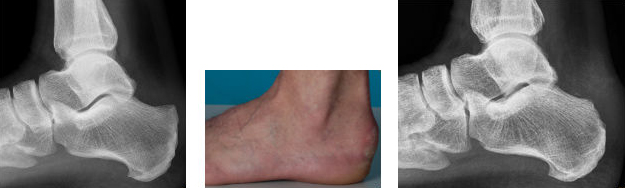

Röntgenbild und Foto vor und nach arthroskopischer Abtragung einer Haglundferse

Eine weitere Indikation stellt die arthroskopische Abtragung sowohl des oberen als auch unteren Fersenspornes dar. Gerade diese Erkrankungen führen zu einer deutlichen Einschränkung der Lebensqualität mit jahrelanger Schmerzanamnese. Die offene Abtragung des Fersenspornes hat auch in der international Literatur aufgrund unkalkulierbarer Ergebnisse praktisch keinen Stellenwert mehr.